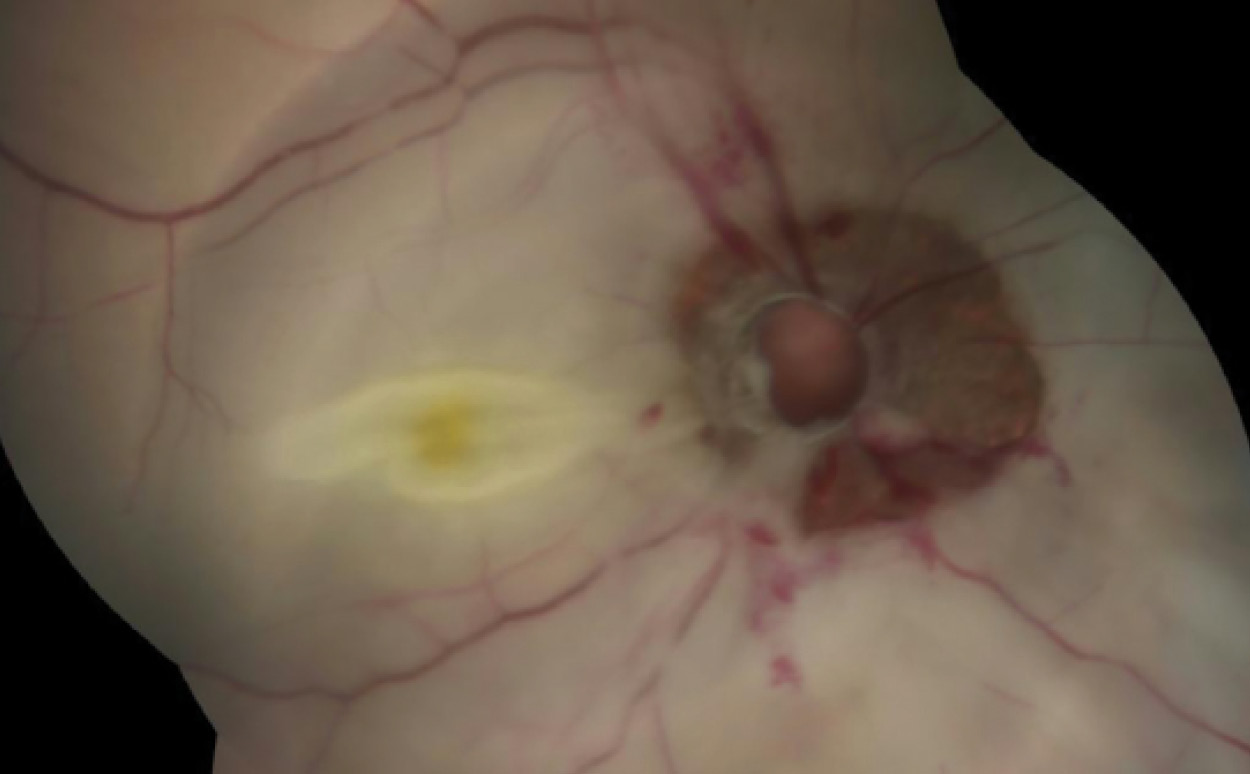

CT scan revealed disruption of the optic nerve at its attachment to the globe, with fluid density in between (image below, right: arrow). A diagnosis of traumatic optic nerve head avulsion with CRAO was established.